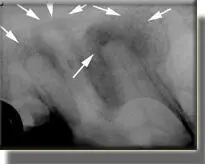

Fractured tooth with no exposure of pulp (nerve) chamber.

Radiographs show large areas of damaged bone, even though the nerve chamber was not exposed by the fracture. According to the owner, this patient acted “years younger” after treatment.